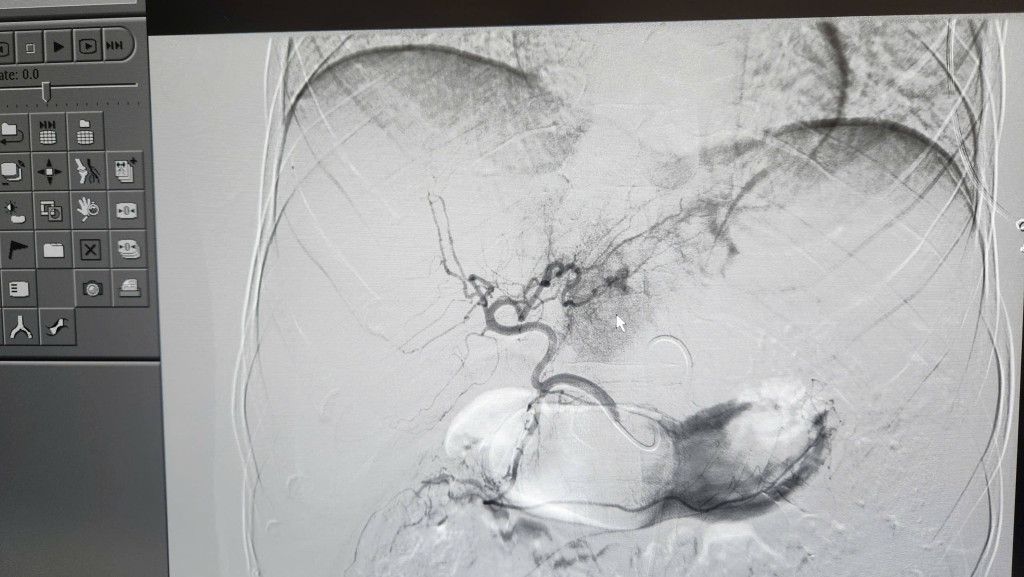

Ê-kíp can thiệp mạch do BSCKII Ngô Vĩnh Hoài - Phó Trưởng khoa Chẩn đoán hình ảnh trực tiếp thực hiện. Dưới sự hỗ trợ của hệ thống chụp mạch số hóa xóa nền (DSA) hiện đại, các bác sĩ đã thao tác chính xác, kiểm soát hoàn toàn điểm chảy máu và cầm máu hiệu quả cho người bệnh.

Các bác sĩ đang thực hiện ca mổ (Ảnh: BVCC)